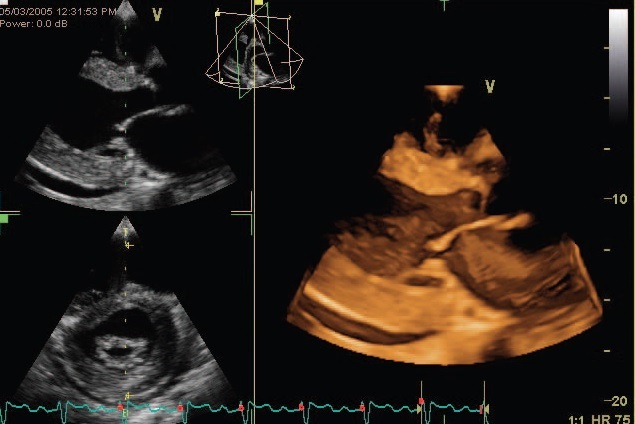

การตรวจหัวใจด้วยคลื่นเสียงสะท้อนระบบ 3 มิติ (3-D Echocardiography) เป็นวิธีการตรวจหัวใจโดยใช้คลื่นเสียงสะท้อนในระบบ 3 มิติ เพื่อการวินิจฉัยโรค รูปที่ได้จะมีความชัดและความลึกแบบ 3 มิติชัดเจนกว่าการตรวจด้วยเครื่องระบบ 2 มิติแบบเก่า

• การทำงานของลิ้นหัวใจที่ผิดปกติทั้งแบบลิ้นหัวใจรั่วและตีบ